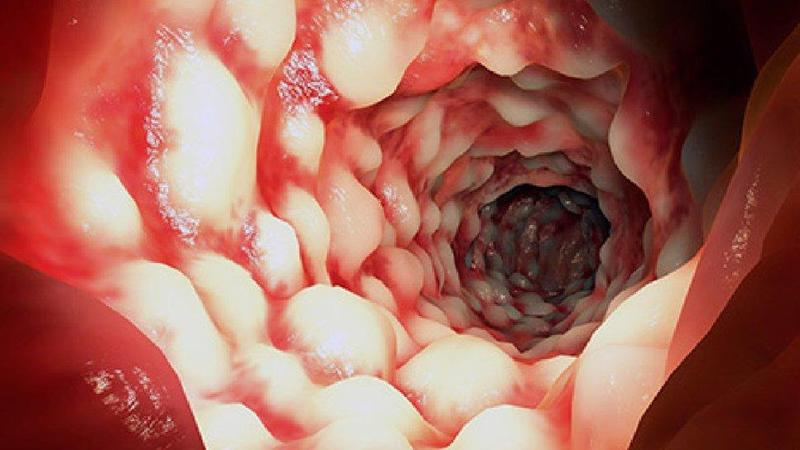

Ulcerative colitis (UC) is an autoimmune disease that causes the immune system to attack the colon, leading to a range of painful signs and symptoms, both in the gastrointestinal (GI) tract and in other parts of the body. The condition causes long-term inflammation of the cells that line the colon, resulting in sores called ulcers. Like most autoimmune diseases, UC has no known cure, but treatment can significantly reduce the signs and symptoms of the disease and possibly even lead to long-term remission.

Blood in the Stool

Seeing blood in your stool is generally always a red flag. This warning sign is common when the inflammation is severe. It could be a result of something simple like an anal fissure or hemorrhoids. Nonetheless, it’s prudent that you visit your doctor, as it could also signal something else is going on.